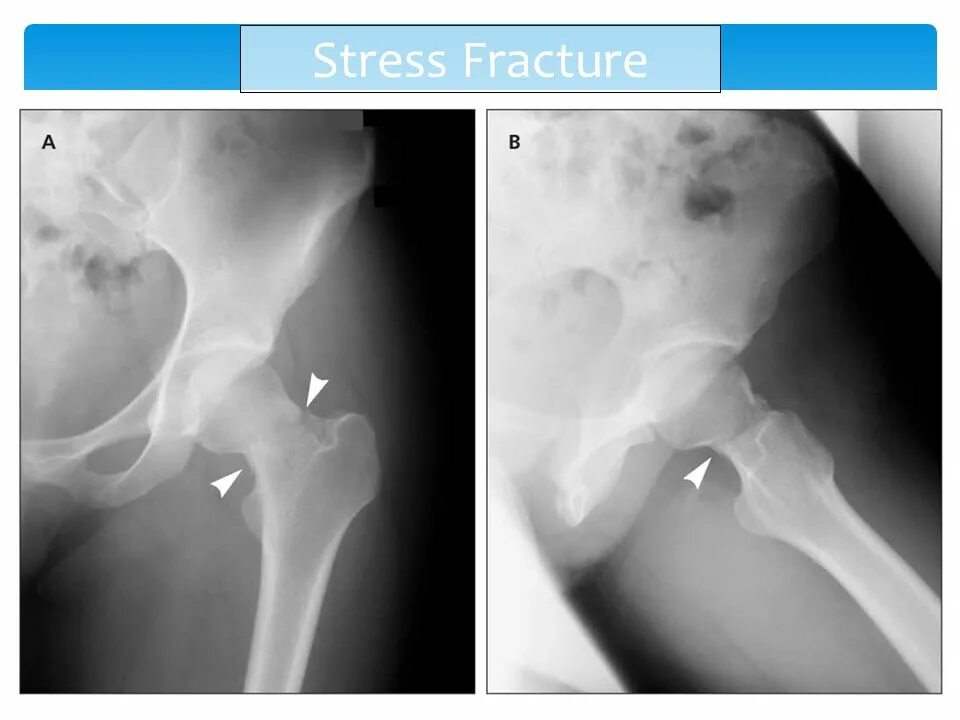

Через перелом бедра